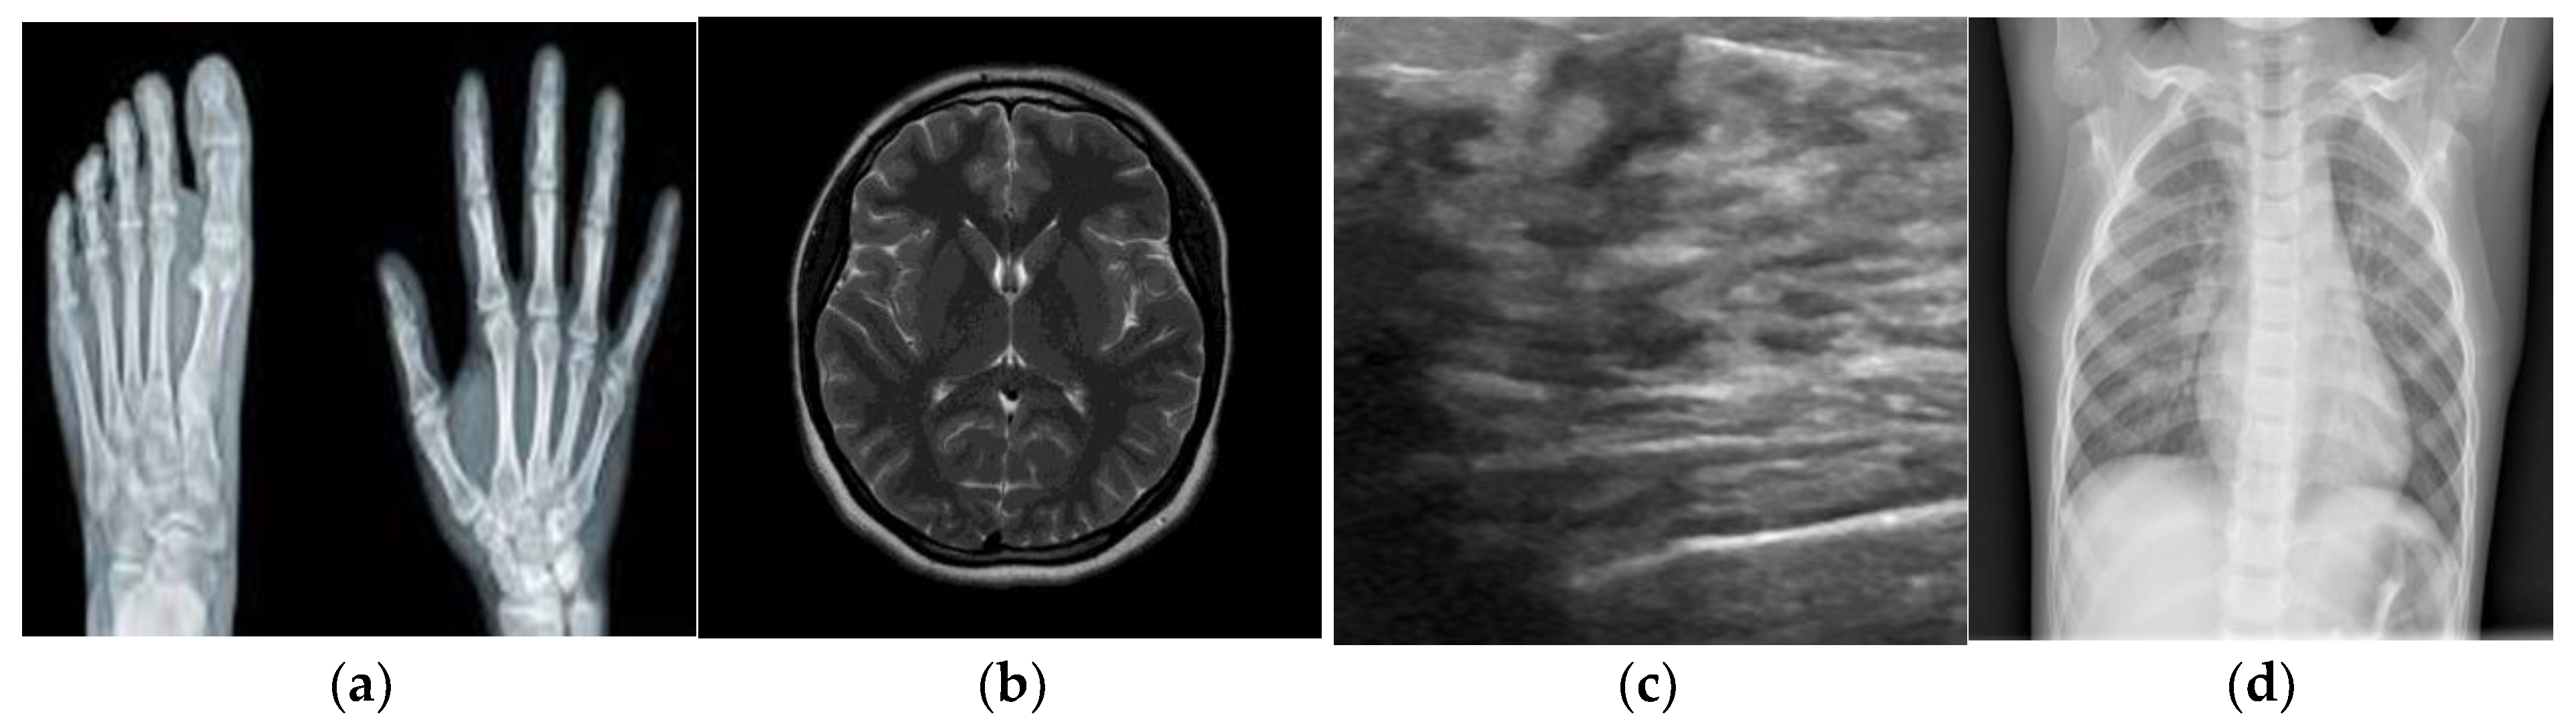

4.2. Visual Analysis